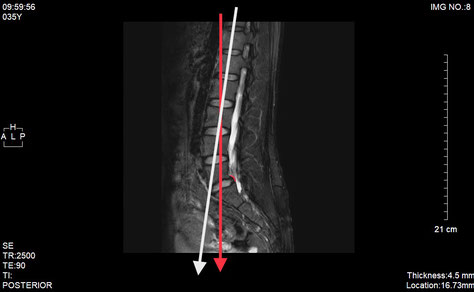

(椎間板ヘルニアとすべり症/ヘルニア消失)

(廃用症候群の徴候)